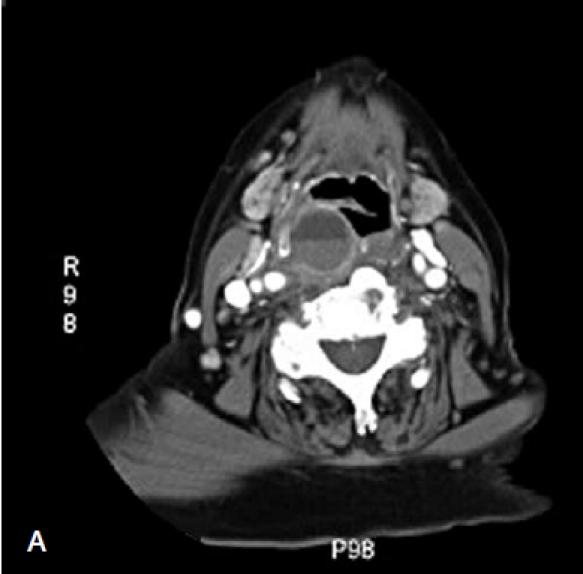

Trans-oesophageal echocardiography is generally considered a safe procedure, but occasional life-threatening complications have been reported. The aim of this clinical investigation is to outline the need of surgical management in cases of large retro-pharyngeal haematoma following trans-oesophageal echocardiography. In the case reported here, a patient with cervical spondylosis on anti-coagulant therapy was referred to the Head and Neck Department because of a retro-pharyngeal haematoma with severe upper airway obstruction following transoesophageal echocardiography. Tracheotomy was required to guarantee respiratory function, while trans-cervical surgery was performed to evacuate the haematoma. Total recovery was achieved within 10 days. In conclusion, the head and neck surgeon should consider the need of surgical management in cases of retro-pharyngeal haematoma following trans-oesophageal echocardiography.

经食管超声心动图通常被认为是一种安全的程序,但偶尔也会发生危及生命的并发症。本临床研究的目的是概述在经食管超声心动图后出现大的咽后血肿时需要手术治疗的情况。在此报告的病例中,一名患有颈椎病且正在抗凝治疗的患者因经食管超声心动图后出现咽后血肿并伴有严重的上呼吸道梗阻而被转至头颈外科。需要进行气管切开术以保证呼吸功能,同时进行经颈手术以清除血肿。患者在 10 天内完全康复。总之,当经食管超声心动图后出现咽后血肿时,头颈外科医生应考虑手术治疗的必要性。